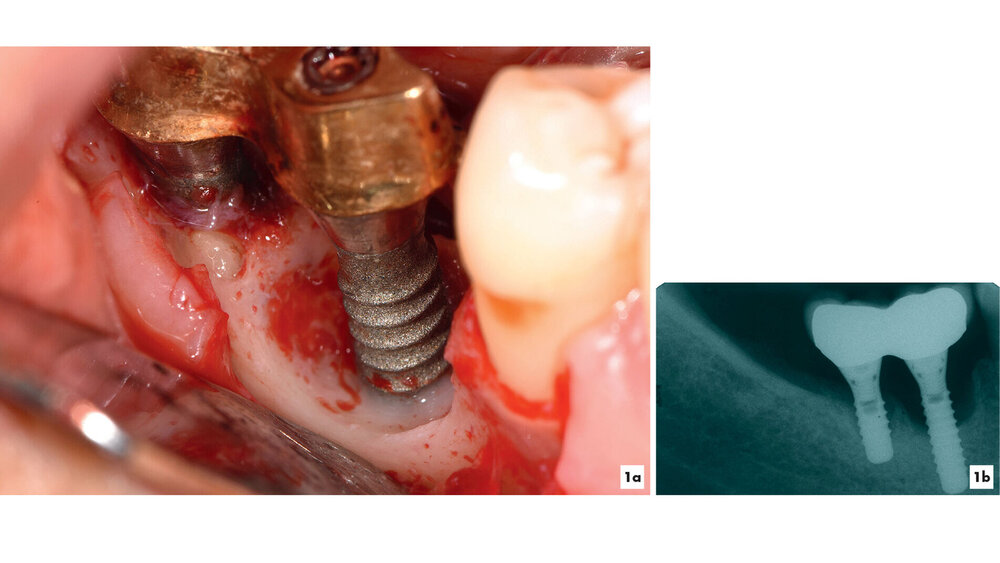

Kommt es jedoch zur Ausbildung einer Inflammation periimplantärer Gewebe ohne Knochenverlust, spricht man von einer periimplantären Mukositis. Wichtigstes Kennzeichen sind dabei die Blutung auf Sondierung und die Begrenzung der Entzündung auf das periimplantäre Saumepithel [Berglundh et al., 2018]. Breitet sich der pathologische Prozess in den Bereich des knöchernen Attachments aus, ist die Destruktion irreversibel und man spricht von einer Periimplantitis (Abbildung 1a). Zusätzlich zu den bereits genannten klinischen Kennzeichen kann man hier auch röntgenologisch den Knochenverlust feststellen, der mit erhöhten Sondierungstiefen und/oder Rezessionen einhergeht [Berglundh, 2019] (Abbildung 1b).